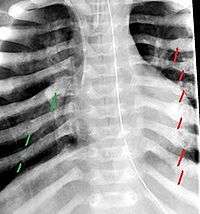

The material factual allegations of the amended complaint are as follows. Plaintiff was born on May 14, 1970. On repeated occasions during the first year of her life she was severely beaten by her mother and the latter’s common law husband, one Reyes. On April 26, 1971, when the plaintiff was eleven months old, her mother took her to the San Jose Hospital for examination, diagnosis, and treatment. The attending physician was defendant Dr. Flood, acting on his own behalf and as agent of the defendant San Jose Hospital. At the time, the plaintiff was suffering from a comminuted spiral fracture of the right tibia and fibula, which gave the appearance of having been caused by a twisting force. Plaintiff’s mother had no explanation for this injury. Plaintiff had bruises over her entire body. In addition, she had a non-depressed linear skull fracture which was then in the process of healing. Plaintiff demonstrated fear and apprehension when approached. Inasmuch as all plaintiff's injuries gave the appearance of having been intentionally inflicted by other persons, she exhibited the medical condition known as the battered child syndrome.

It is alleged that proper diagnosis of plaintiff's condition would have included taking X-rays of her entire skeletal structure, and that such procedure would have revealed the fracture of her skull. Defendants negligently failed to take such X-rays, and thereby negligently failed to diagnose her true condition. It is further alleged that proper medical treatment of plaintiff's battered child syndrome would have included reporting her injuries to local law enforcement authorities or juvenile probation department. Such a report would have resulted in an investigation by the concerned agencies, followed by a placement of plaintiff in protective custody until her safety was assured. Defendants negligently failed to make such report.

While helpful, the foregoing general history of the battered child syndrome is not conclusive on the precise question in the case at bar. The question is whether a reasonably prudent physician examining this plaintiff in 1971 would have been led to suspect she was a victim of the battered child syndrome from the particular injuries and circumstances presented to him, would have confirmed that diagnosis by ordering X-rays of her entire skeleton, and would have promptly reported his findings to appropriate authorities to prevent a recurrence of the injuries. There are numerous recommendations to follow each of these diagnostic and treatment procedures in the medical literature cited above.

For example, the leading article by Kempe et al., op. cit., supra,[9] states that "A physician needs to have a high initial level of suspicion of the diagnosis of the battered-child syndrome in instances of subdural hematoma, multiple unexplained fractures at different stages of healing, failure to thrive, when soft tissue swelling or skin bruising are present, or in any other situation where the degree and type of injury is at variance with the history given regarding its occurrence . . . ." (Id., at p. 20.) Of the different types of fractures exhibited, an arm or leg fracture caused by a twisting force is particularly significant because "The extremities are the 'handles' for rough handling" of the child by adults. (Id., at p. 22.) The article also contains numerous recommendations to conduct a "radiologic examination of the entire skeleton" for the purpose of confirming the diagnosis, explaining that "To the informed physician, the bones tell a story the child is too young or too frightened to tell." (Id., at p. 18.) Finally, on the subject of management of the case it is repeatedly emphasized that the physician "should report possible willful trauma to the police department or any special children's protective service that operates in his community" (id., at p. 23) in order to forestall further injury to the child: "All too often, despite the apparent cooperativeness of the parents and their apparent desire to have the child with them, the child returns to his home only to be assaulted again and suffer permanent brain damage or death." (Id., at p. 24.)